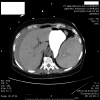

Results: Neither a history of abdominal surgery nor performance of a biopsy seems related to an increased incidence of splenic injury. However, a number of colonoscopy-related factors, such as difficulty intubating, looping of the instrument, and traction on the splenocolic ligament, lead to capsular avulsions and lacerations of the spleen. In addition, excess external pressure on the left hypochondrium can simulate blunt trauma, and other maneuvers can increase traction at the splenic flexure. In the majority of cases, symptoms develop within 24 hours of the colonoscopy. Computed tomography scan provides the most sensitive and specific method of diagnosis.